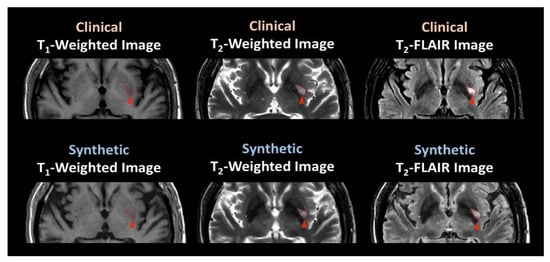

3.2. Participant Evaluation